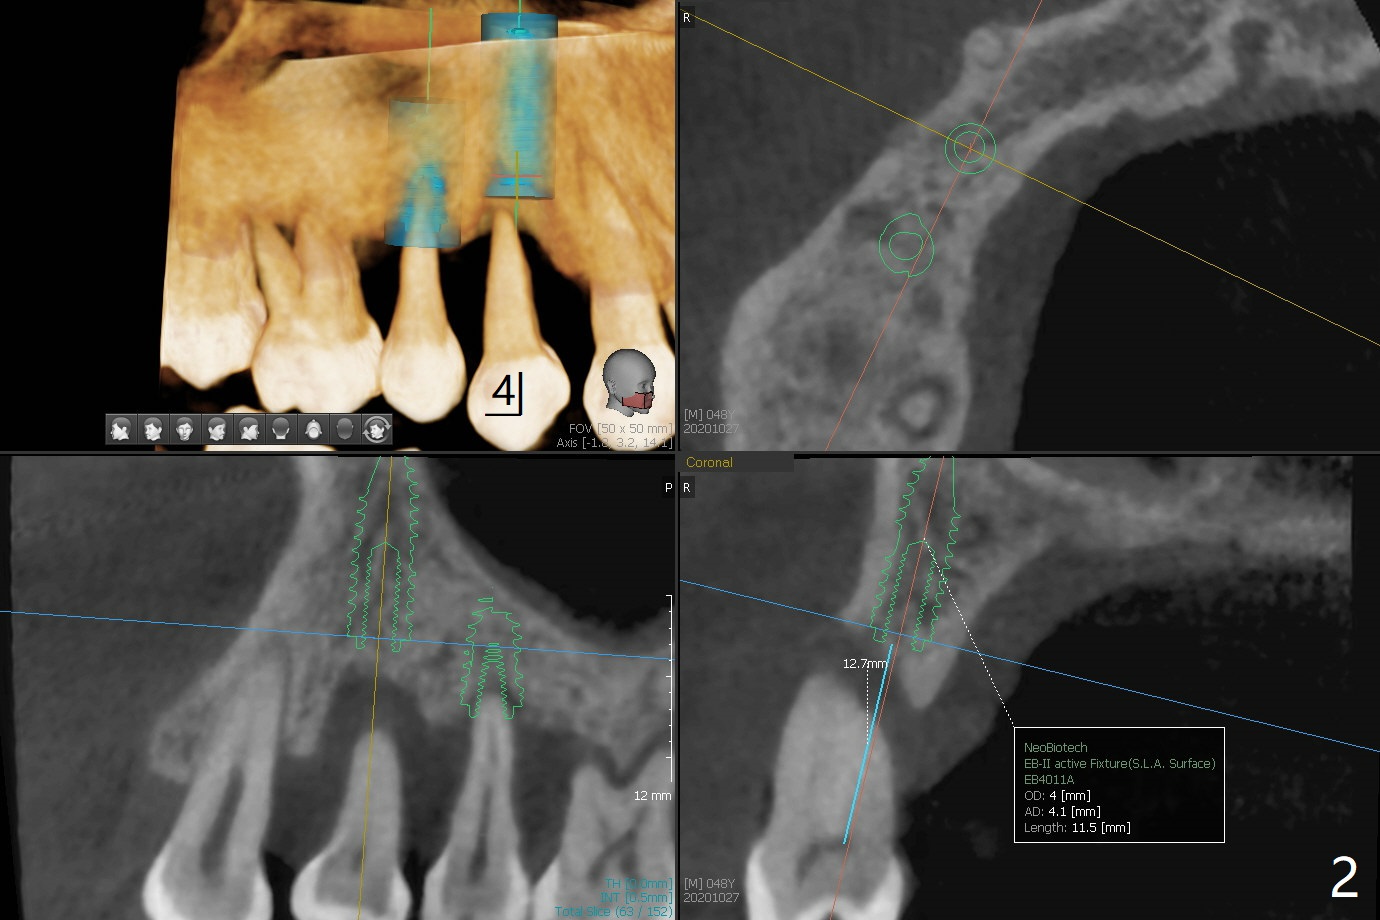

术前CT显示右上4牙槽骨比5窄(图一,二),3.5毫米植体比较合适,况且牙龈厚,基台长的一段式植体显得得当。为了取得最好的植体方位,4先拔除(图三),种植(图四),调整后者深度后,拔除5(术前征求病人同意),开始钻洞(图五),完成种植(图六)。粘性骨粉不仅放置于植体周围,而且6牙根近中(图七),4/5牙槽嵴和龈乳头(P)之间,减少术后龈乳头萎缩(图八:*)。制作两个分开临时牙冠,有利于维持龈乳头。对于病人来说,临时牙冠帮助咀嚼,而对侧拔牙创无法吃饭。术后3个月两个分开临时牙冠(其中一个龈方移位(图九:箭头)保持龈乳头(*)和牙龈外形(图十:*)。临时牙冠取出后,调整基台高度,少量钛屑(不妨大局)附着在健康的牙龈沟(图十一),再次显示两个基台之间龈乳头(图十二:*),衬里,修整的临时牙冠又插回牙龈沟(图十三:箭头),继续维持软组织形态,准备一个月后,调整基台边缘(图十二:箭头),取模。术后五个月大部分骨粉依然保留在植体和邻牙周围,龈乳头退缩不多(图十四: P)。三个月后(术后六个月)钛削无影无踪(图十五,与图十一对比))。永久性牙冠周围空间慢慢会消失(图十六,使用临时性胶水)。